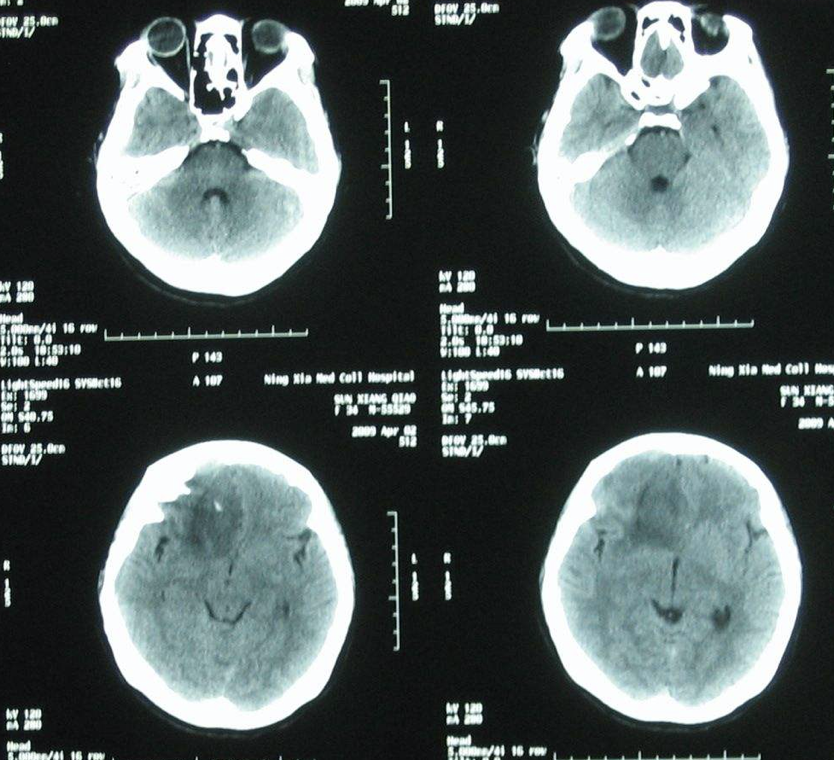

人们所说的“脑癌”通常指的是脑肿瘤,又称颅内肿瘤,它是指生长在颅腔的新生物,可起源于脑、脑膜、神经、血管及脑附件,或由身体的其他组织或脏器转移侵入颅内而形成,可产生头痛、颅内高压及局灶性症状。

一旦发现脑肿瘤,目前公认的治疗手段为开颅手术切除肿瘤,而放射治疗、药物治疗仅适用于一部分患者,或者作为手术后的补充治疗手段。脑肿瘤手术常采用显微手术,简单说就是在手术显微镜下操作,把手术视野放大7~10倍,使手术的细致程度大大提高,不仅使肿瘤切除得更为完全,同时较大水平的保留了主要的神经和血管,减少了对正常脑组织的损伤,手术的疗效大大提高。